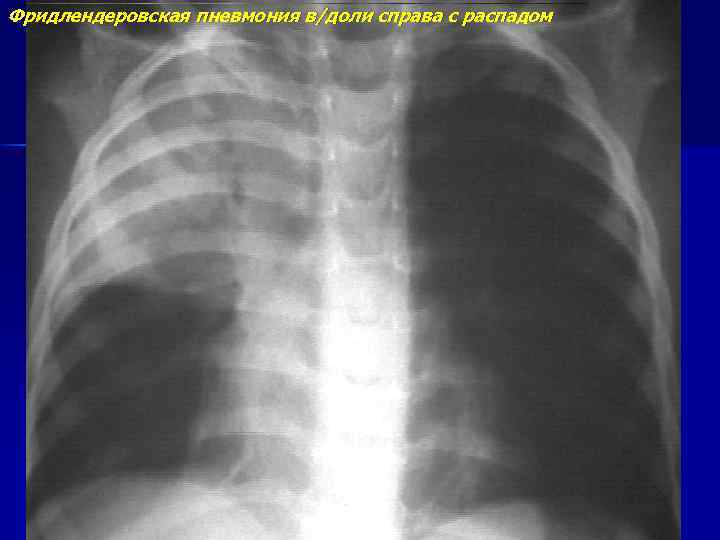

Фридлендеровская пневмония

Фридлендеровская пневмония в/доли справа с распадом